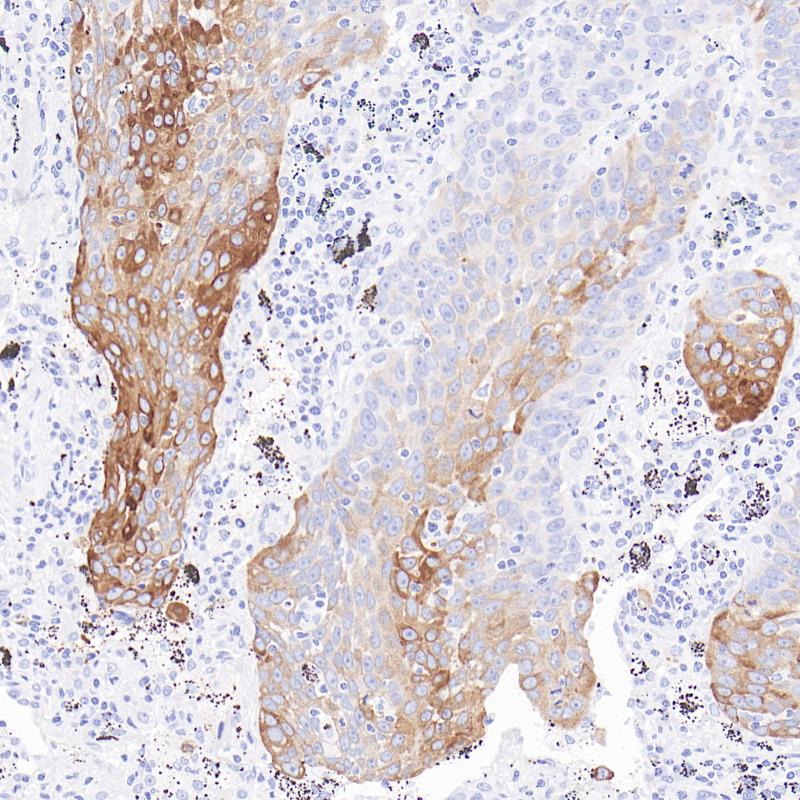

PMEL 17 重组兔单克隆抗体

阳性对照

黑色素瘤

亚细胞定位

细胞质